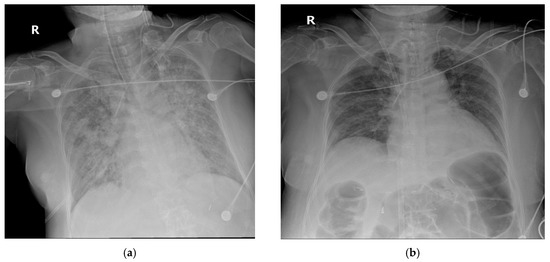

2.1. Case 1

2.2. Case 2

2.3. Case 3